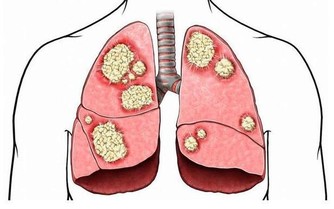

和其他任何惡性腫瘤一樣,腦瘤也是非常可怕的。它可以分為原發性腦瘤和繼發性腦瘤。

原發性腦腫瘤是那些一開始並在大腦中存在的腫瘤,並不常見。

而繼發性腦瘤,是從其他部位(如乳房或肺部)擴散到大腦的癌性生長。

大部分腦腫瘤都屬於這種類型。